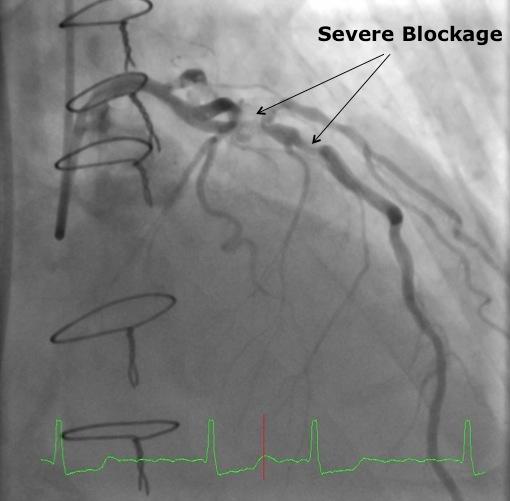

An echocardiogram revealed severe aortic insufficiency. In addition, a diagnostic cardiac catheterization showed single-vessel coronary artery disease involving the left anterior descending (LAD) coronary artery. The development of recurrent CAD over time was compromising the patient’s initial bypass procedure, and represented a significant cardiac event risk.

“After seeing the patient and reviewing his history, I determined he was an excellent candidate for reoperative surgery.  Because his problem was aortic insufficiency with no calcific stenosis, he was not a candidate for a transcatheter aortic valve” says Kern. “I considered the option of doing a redo LAD bypass along with the valve replacement, but that would have slightly increased the operative risk. I reviewed his cath with Dr. Ragosta to see if stenting the LAD prior to surgical valve replacement was an option, in order to minimize the surgical dissection and risk.”

Dr. Ragosta performed a minimally invasive cardiac catheterization through the patient’s radial artery, placing a bare-metal stent into the LAD with excellent angiographic results. Because of the need for Plavix, surgery was delayed for at least four weeks.